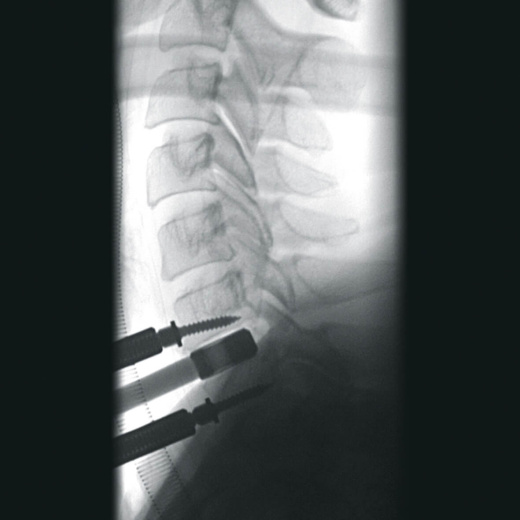

- вертебрология,

Автораспознавание металла

Винты, пластины, импланты и хирургические инструменты автоматически распознаются при попадании в видимое поле аппарата. В этом случае происходит корректировка мощности дозы облучения для улучшения качества снимка.